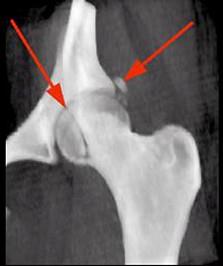

问题 女,35岁,摔伤后左髋部剧痛,活动受限6小时,请结合影像学检查,选出最可能的诊断 ( )

选项 A、加莱阿奇骨折 B、肱骨骨折 C、股骨头骨折 D、骨盆骨折 E、股骨颈骨折

答案 C